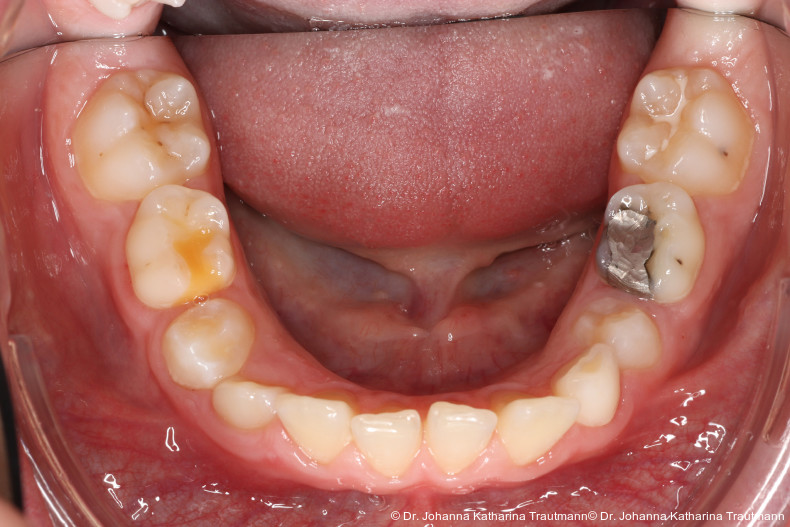

Das Fernröntgenseitenbild zeigte eine skelettale Klasse IIAnomalie mit einem Wits von 5,6 mm, bei einer tiefen Konfiguration (ML NL = 16,5°) mit bialveolär retrudierten Fronten (OK1NA = 5,9°; UK1NB = 10,4°), was sich auch in der Modellanalyse widerspiegelte. Hier zeigte sich zudem ein schmaler Oberkiefer mit multiplen Kippungen und Rotationen in der Front, einem hypoplastischem 22 sowie einer Mesialwanderung des 16. Des Weiteren zeigte sich eine asymmetrische Bisslage mit 1 PB distal rechts und ½ PB distal links bei einem Overjet von 2,5 mm sowie einem Overbite von 5 mm. Während im Unterkiefer bereits die zweite Zahnwechsel phase begonnen hatte, zeigte sich im Oberkiefer noch kein Wechsel in den Stützzonen. Gerade bei Patienten mit Spaltbildungen ist eine engmaschige Überwachung des Durchbruchs der oberen Eckzähne essenziell. Während bei der Allgemeinbevölkerung die Prävalenz von verlagerten Eckzähnen bei ca. 2,8 Prozent liegt2, ist diese bei Patienten mit Lippen-Kiefer-Gaumen-Spalten um den Faktor 10 erhöht.3, 4 Als klassische Risikofaktoren gelten zudem Platzmangel, transversale Enge aber auch Fehlstellungen, Nichtanlagen oder Hypoplasien der zweiten Schneidezähne. Diese übernehmen normalerweise die Funktion der Leitschiene für den S-förmigen Durchbruch der Eckzähne. Im vorliegenden Patientenfall kommen also mehrere Risikofaktoren für eine Verlagerung zusammen, was die rechtzeitige Diagnostik zur Abklärung einer Durchbruchsproblematik rechtfertigt. Da im Spaltbereich auch zusätzlich ein ausgeprägtes Knochendefizit vorliegen könnte, sollte auch immer die Option einer sekundären Osteoplastik abgewogen werden, deren Indikation und Timing optimal zum Durchbruch der Canini angepasst werden sollte.5

Nach transversaler Nachentwicklung der Maxilla mittels GNE nach Veltri wurde der Zahn 23 geschlossen freigelegt und an einem individualisier ten TPA nach distal angebunden. Zur Aufrichtung der Front und Mesialisierung des hypoplastischen Zahnes 22 kam zusätzlich eine 2x3Mechanik zum Einsatz. Eine rein translatorische Bewegung eines Zahnes ist auch mit einer festsitzenden Apparatur schwer zu erreichen, da der Kraftansatzpunkt nicht identisch mit dem Widerstandszentrum des Zahnes ist.7 Diese Problematik kann einerseits durch das Einbringen eines Versetzungsmomentes adressiert werden, andererseits durch eine Verlagerung des Kraftansatzpunktes. Angelehnt an den von Hong et al. beschriebenen Power Arm 8 wurde hierfür palatinal an Zahn 22 ein cranial gerichteter Hook angebracht (Abb. 3). Da Zahn 22 aufgrund seiner Hypoplasie eine verkürzte Wurzel aufwies, konnte so die Distanz zwischen Widerstandszentrum und Kraftangriffspunkt effizient reduziert werden. Eine weitere biomechanische Schwierigkeit stellte das geringe Alveolarknochenangebot im Spalt bereich mesial von 22 dar. In Bereichen mit Knochendefizit verschiebt sich das Widerstandszentrum nach apikal und wie in diesem Fall zusätzlich nach distal.9, 10 Um dem erhöhten Risiko für Kipp bewegungen entgegenzuwirken, muss hier besonders auf die Steuerung des M/F-Quotienten geachtet werden. Der vestibulär durchgebrochene Zahn 13 benötigte keine Freilegung. Um seine korrekte Einstellung zu ermöglichen, wurde die Mesialwanderung des Zahnes 16 mithilfe des TPAs korrigiert sowie eine Mittellinienkorrektur nach links mittels 2x3 Mechanik durchgeführt.

Im Rahmen der Multibrackettherapie wurde bewusst der Zahn 13 aus dem Hauptnivellie rungsbogen ausgelassen, um Kippungen und Asymmetrien im Zahnbogen zu vermeiden. Der Zahn 23 wurde locker mit einer Distanz ligatur angebunden, um eine weitere Bewegung nach vestibulär zu erreichen. Auf einem 0.019" x 0.025" Stahlbogen erfolgte anschlie ßend mittels Umgehungsbiegung sowie eines Overlaybogens (0.014" NiTi) die Integration des Zahnes 13 in den Zahnbogen. Die Zwischendiagnostik nach einem Jahr festsitzender Behandlung zeigte eine gelungene Bisshebung bei guter Nivellierung des Okklusionsplanums und orthoaxialer Einstellung der Frontzähne. Die Zahnbögen präsentierten sich harmonisch ausgeformt, es zeigte sich jedoch eine verbleibende Torqueproblematik an bei den Oberkiefereckzähnen. Nach Freilegung und Einstellung verlagerter Eckzähne ist eine korrekte Torque und Angulationssteuerung häufig eine Herausforderung. Während vestibulär verlagerte Zähne zu gingivalen Rezessionen neigen, behalten palatinal verlagerte Zähne oft ihre palatinale Wurzelstellung bei.13, 14 Die genutzte MBTPrescription der Brackets bietet die Möglichkeit, zwischen +7°, 0° und –7° Torque zu wählen.15 In einem 0.022" System ist bei Verwendung eines 0.019" x 0.025" Bogens jedoch mit einem Torqueverlust von etwa 10° zu rechnen.16